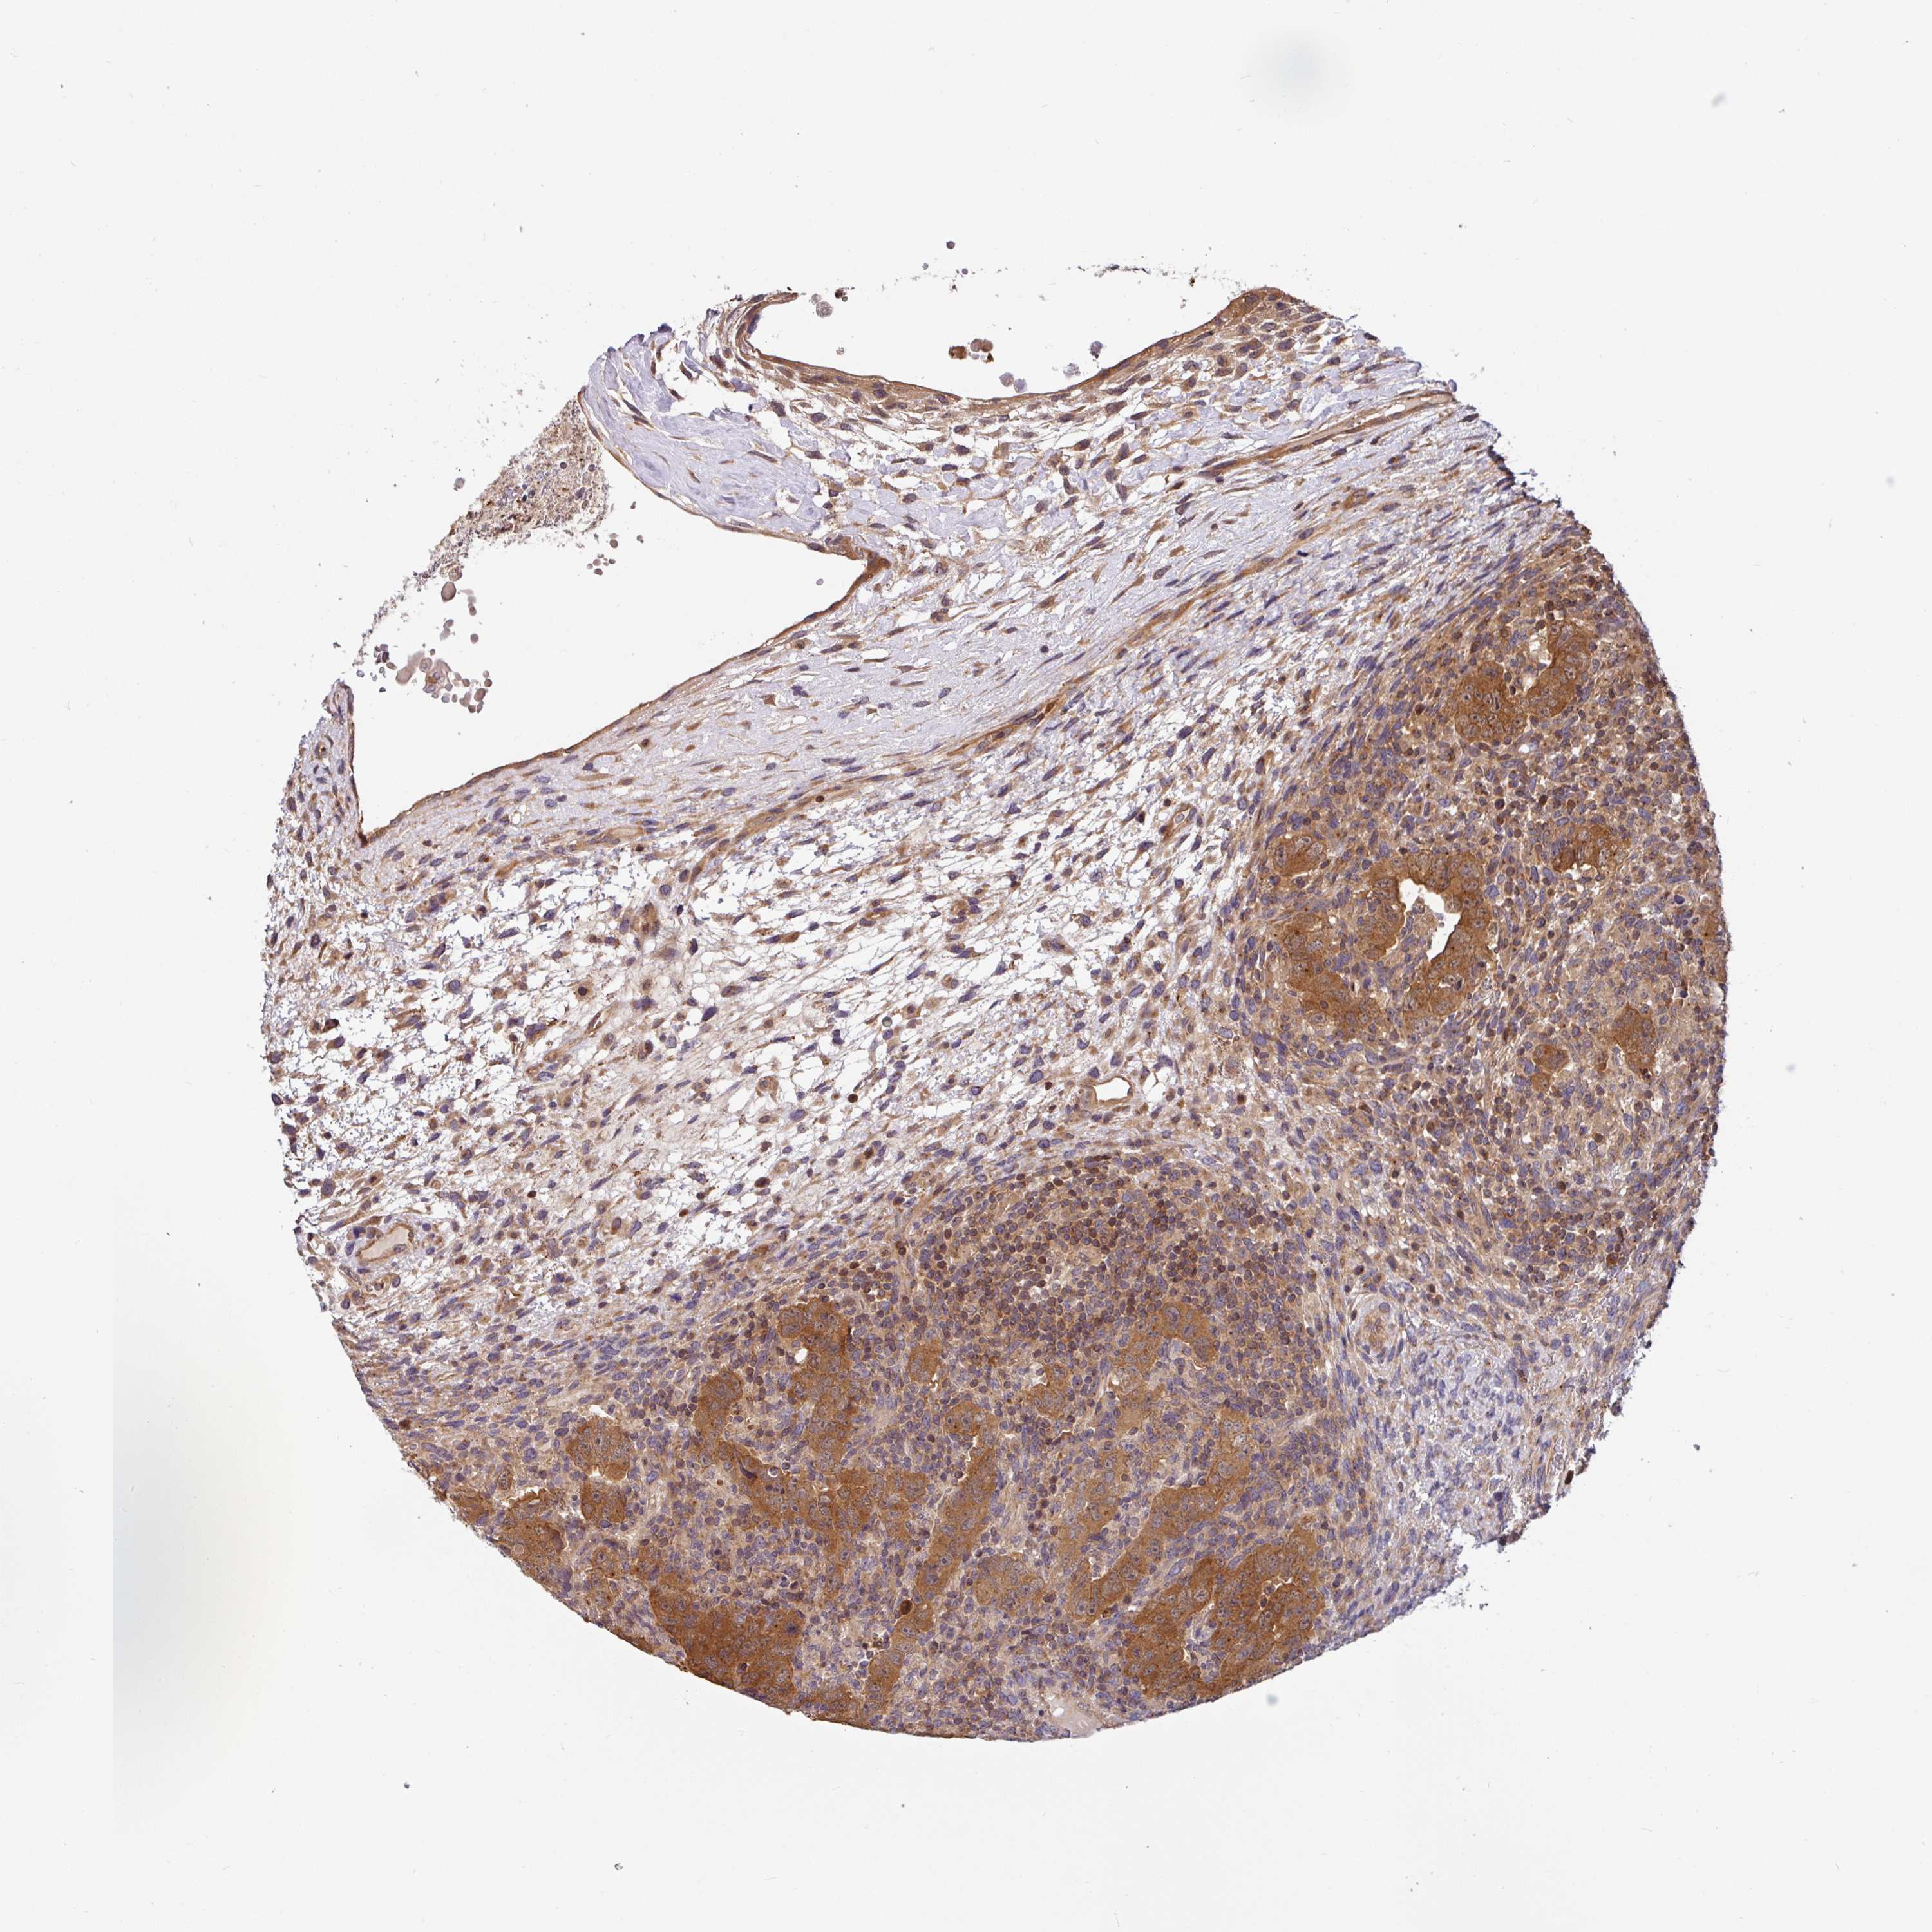

TESTIS CANCER - Protein expressioni

A mouse-over function shows sample information and annotation data. Click on an image to view it in a full screen mode. Samples can be filtered based on level of antibody staining by selecting one or several of the following categories: high, medium, low and not detected. The assay and annotation is described here.

Note that samples used for immunohistochemistry by the Human Protein Atlas do not correspond to samples in the TCGA dataset.

Antibody stainingi

Antibody staining in the annotated cell types in the current human tissue is reported as not detected, low, medium, or high, based on conventional immunohistochemistry profiling in selected tissues. This score is based on the combination of the staining intensity and fraction of stained cells.

Each image is clickable and will lead to virtual microscopy that enables deeper exploration of all samples and also displays staining intensity scores, fraction scores and subcellular localization as well as patient and tissue information for each sample.

Antibody HPA049911

Antibody CAB010161

Seminoma, NOS

Carcinoma, Embryonal, NOS

Teratoma, malignant, NOS